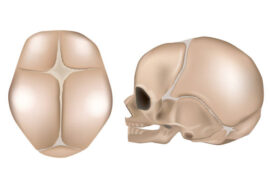

ينمو رأس الطفل بسرعة كبيرة خلال الأشهر الأولى من الحياة، خاصة خلال أول سبعة أشهر، حيث ينمو الدماغ بشكل متسارع. بعد عمر سنة يبدأ معدل النمو بالتباطؤ، وبحلول عمر سنة ونصف تقريبًا يصبح شكل الرأس شبه ثابت.

هذا يعني أن الفترة الذهبية لتعديل شكل الرأس أو التدخل العلاجي – إن لزم – تكون خلال السنة الأولى، خصوصًا في الأشهر الستة الأولى.

هل تشوه شكل الرأس وراثي؟

في أغلب الحالات، تشوه شكل الرأس عند الرضع يكون وضعيًا، أي ناتجًا عن ضغط خارجي بسبب وضعية النوم أو الاستلقاء.

لكن في حالات نادرة جدًا، قد يكون هناك سبب وراثي أو خلل خلقي في عظام الجمجمة يؤدي إلى تشوه الرأس. لذلك من المهم استشارة طبيب مختص إذا كان هناك تاريخ عائلي أو إذا بدا التشوه غير معتاد.